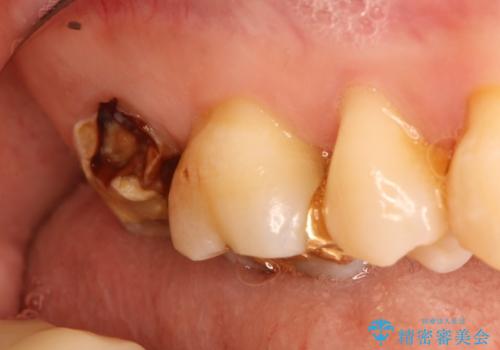

- 虫歯の治療を希望され来院された患者様です。

根管治療を行いオールセラミッククラウンによる治療を行いました。(根管治療は林先生に依頼)

歯肉の下にも虫歯が広がっており歯周外科を行った後、被せもの治療を行いました。